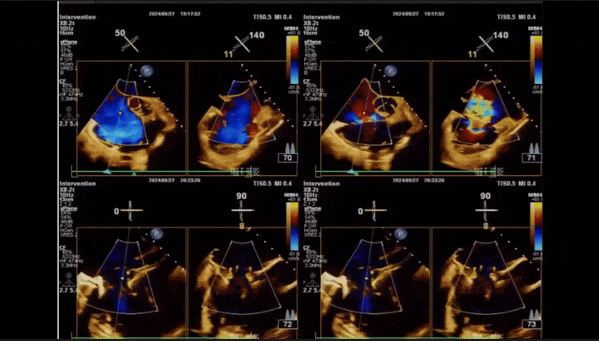

術(shù)前TEE評估

1、3D TEE顯示雙房及右室擴(kuò)大,右室中段直徑40mm,右室FCA 52%。三尖瓣環(huán)TAPSE 22mm,三尖瓣環(huán)左右徑49mm,三尖瓣隔葉長度16mm,前葉長度21mm,后葉長度34mm,三尖瓣前隔gap 11mm,后隔gap 5.6mm,AP gap 12mm,診斷極重度功能性三尖瓣返流(Type I型三尖瓣:Torrential FTR 5+)。

2、彩色多普勒顯示:收縮期三尖瓣口返流束起源于后隔交界、前后葉之間及前隔交界,返流束縮流頸最大寬度27mm,三尖瓣返流口EOA=2.02cm2,返流容積124ml,收縮期三尖瓣返流峰值速度2.64m/s,返流峰值壓差28mmHg,PAPs 43mmHg,舒張期三尖瓣口平均跨瓣壓差1mmHg,肝左靜脈可見明顯逆向血流波。

術(shù)后即刻返流

術(shù)后即刻返流三維

術(shù)中經(jīng)食道超聲輔助下可見LuX-Valve Plus夾持件抓捕瓣葉狀態(tài)良好,夾持件在位,室間隔錨定位置良好,假體瓣膜整體錨定狀態(tài)穩(wěn)固。

術(shù)后三維超聲

術(shù)后即刻經(jīng)食道超聲可見,三尖瓣假體瓣膜位置合適,牛心包瓣葉運(yùn)動狀態(tài)良好,開閉正常,瓣周及瓣葉對合緣處未見明顯返流,心電圖及心包狀態(tài)較術(shù)前無明顯變化。